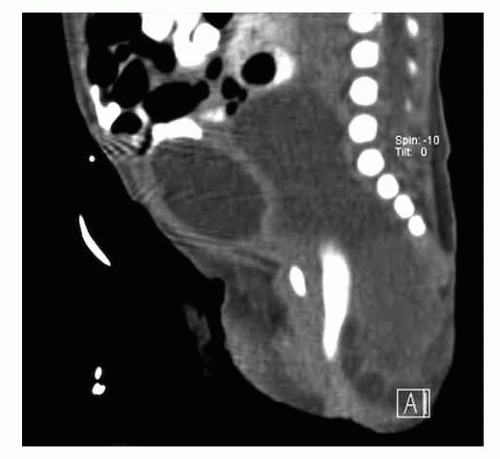

Most SCTs are diagnosed prenatally at the time of approximately 20-week gestation fetal anatomy ultrasound. If diagnosed, the mother and fetuses should be referred to a high-volume multidisciplinary fetal diagnosis and treatment center where a high-resolution fetal ultrasound will be performed to assess the anatomical extension of the tumor and the characteristics of the mass (solid, cystic, vascularity) (FIG 1A).

After birth, hemodynamically stable infants may undergo a CT scan or MRI to assess the extent of the tumor for preoperative planning (FIG 2).